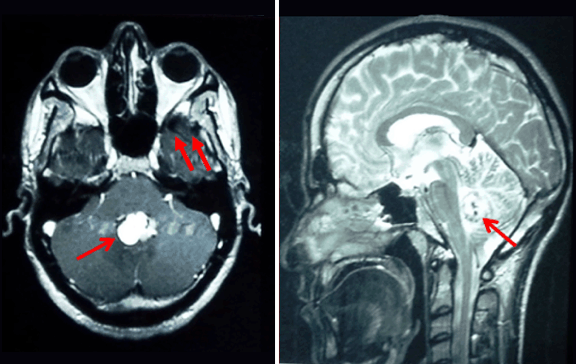

Cover Figure

Magnetic resonance imaging scan of the brain showing a vermian hemangioblastoma associated with 2 small right cerebellar hemangioblastomas. (Page 398)